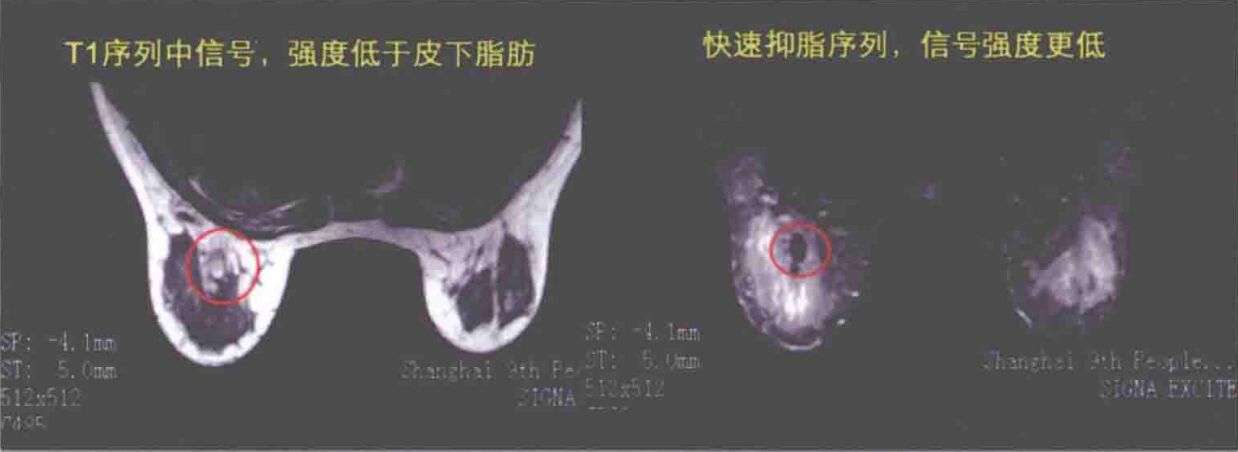

③MRI的表现:由于坏死脂肪的分布、包囊的厚薄有差异,移植脂肪坏死形态在MRI中的表现也是多样的。MRI表现为与术前对比,分布于皮下、腺体内、腺体后方或胸大肌内的新增信号区。为圆形、椭圆形、条状、杵状或不规则型。杵状病损长轴方向与脂肪注射方向相一致。上述病损在超声中可能有显示,也可能显现不出;在钼靶中也可能有不能显现的。病损在磁共振上的表现是包膜可见或不可见。包膜在T,wI序列中呈等信号,T2抑脂中呈低信号,T2WI呈低信号,STIR序列中呈低信号。内容物在T,wI序列中呈高信号,T2抑脂中呈低信号或高信号,T2WI呈高信号,STIR序列中呈高信号。

有时囊肿内见液平,液平面上方物质呈脂肪信号;有时表现为病损周围2~5mm厚的低信号影。如进行增强摄片时,T2抑脂,sTIR序列中病损处明X低信号。其乳房磁共振表现为左右乳房欠对称,皮下层欠清晰,乳腺结构紊乱;胸大肌肿胀,乳腺内见数个团状、T,低信号,T2、T2抑脂,STIR高信号影,部分团块影内见液平,液平面上方物质呈脂肪信号。如有乳房感染,早期移植脂肪坏死的情况包括包裹、液平、水肿3个影像特征。